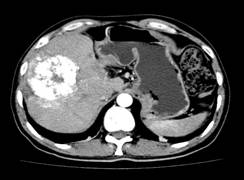

张××,男,56岁,外院CT增强示肝右叶“巨块型肝癌”,首次介入治疗后复查CT(2012年4月25日)所见瘤体大部栓塞,周围组织损伤小(图1a~b)。3年9个月后复查(2016年1月21日)见原瘤体明显缩小,上方肝实质复发病灶(图2a~b)。

图1a 图1b

图2a 图2b